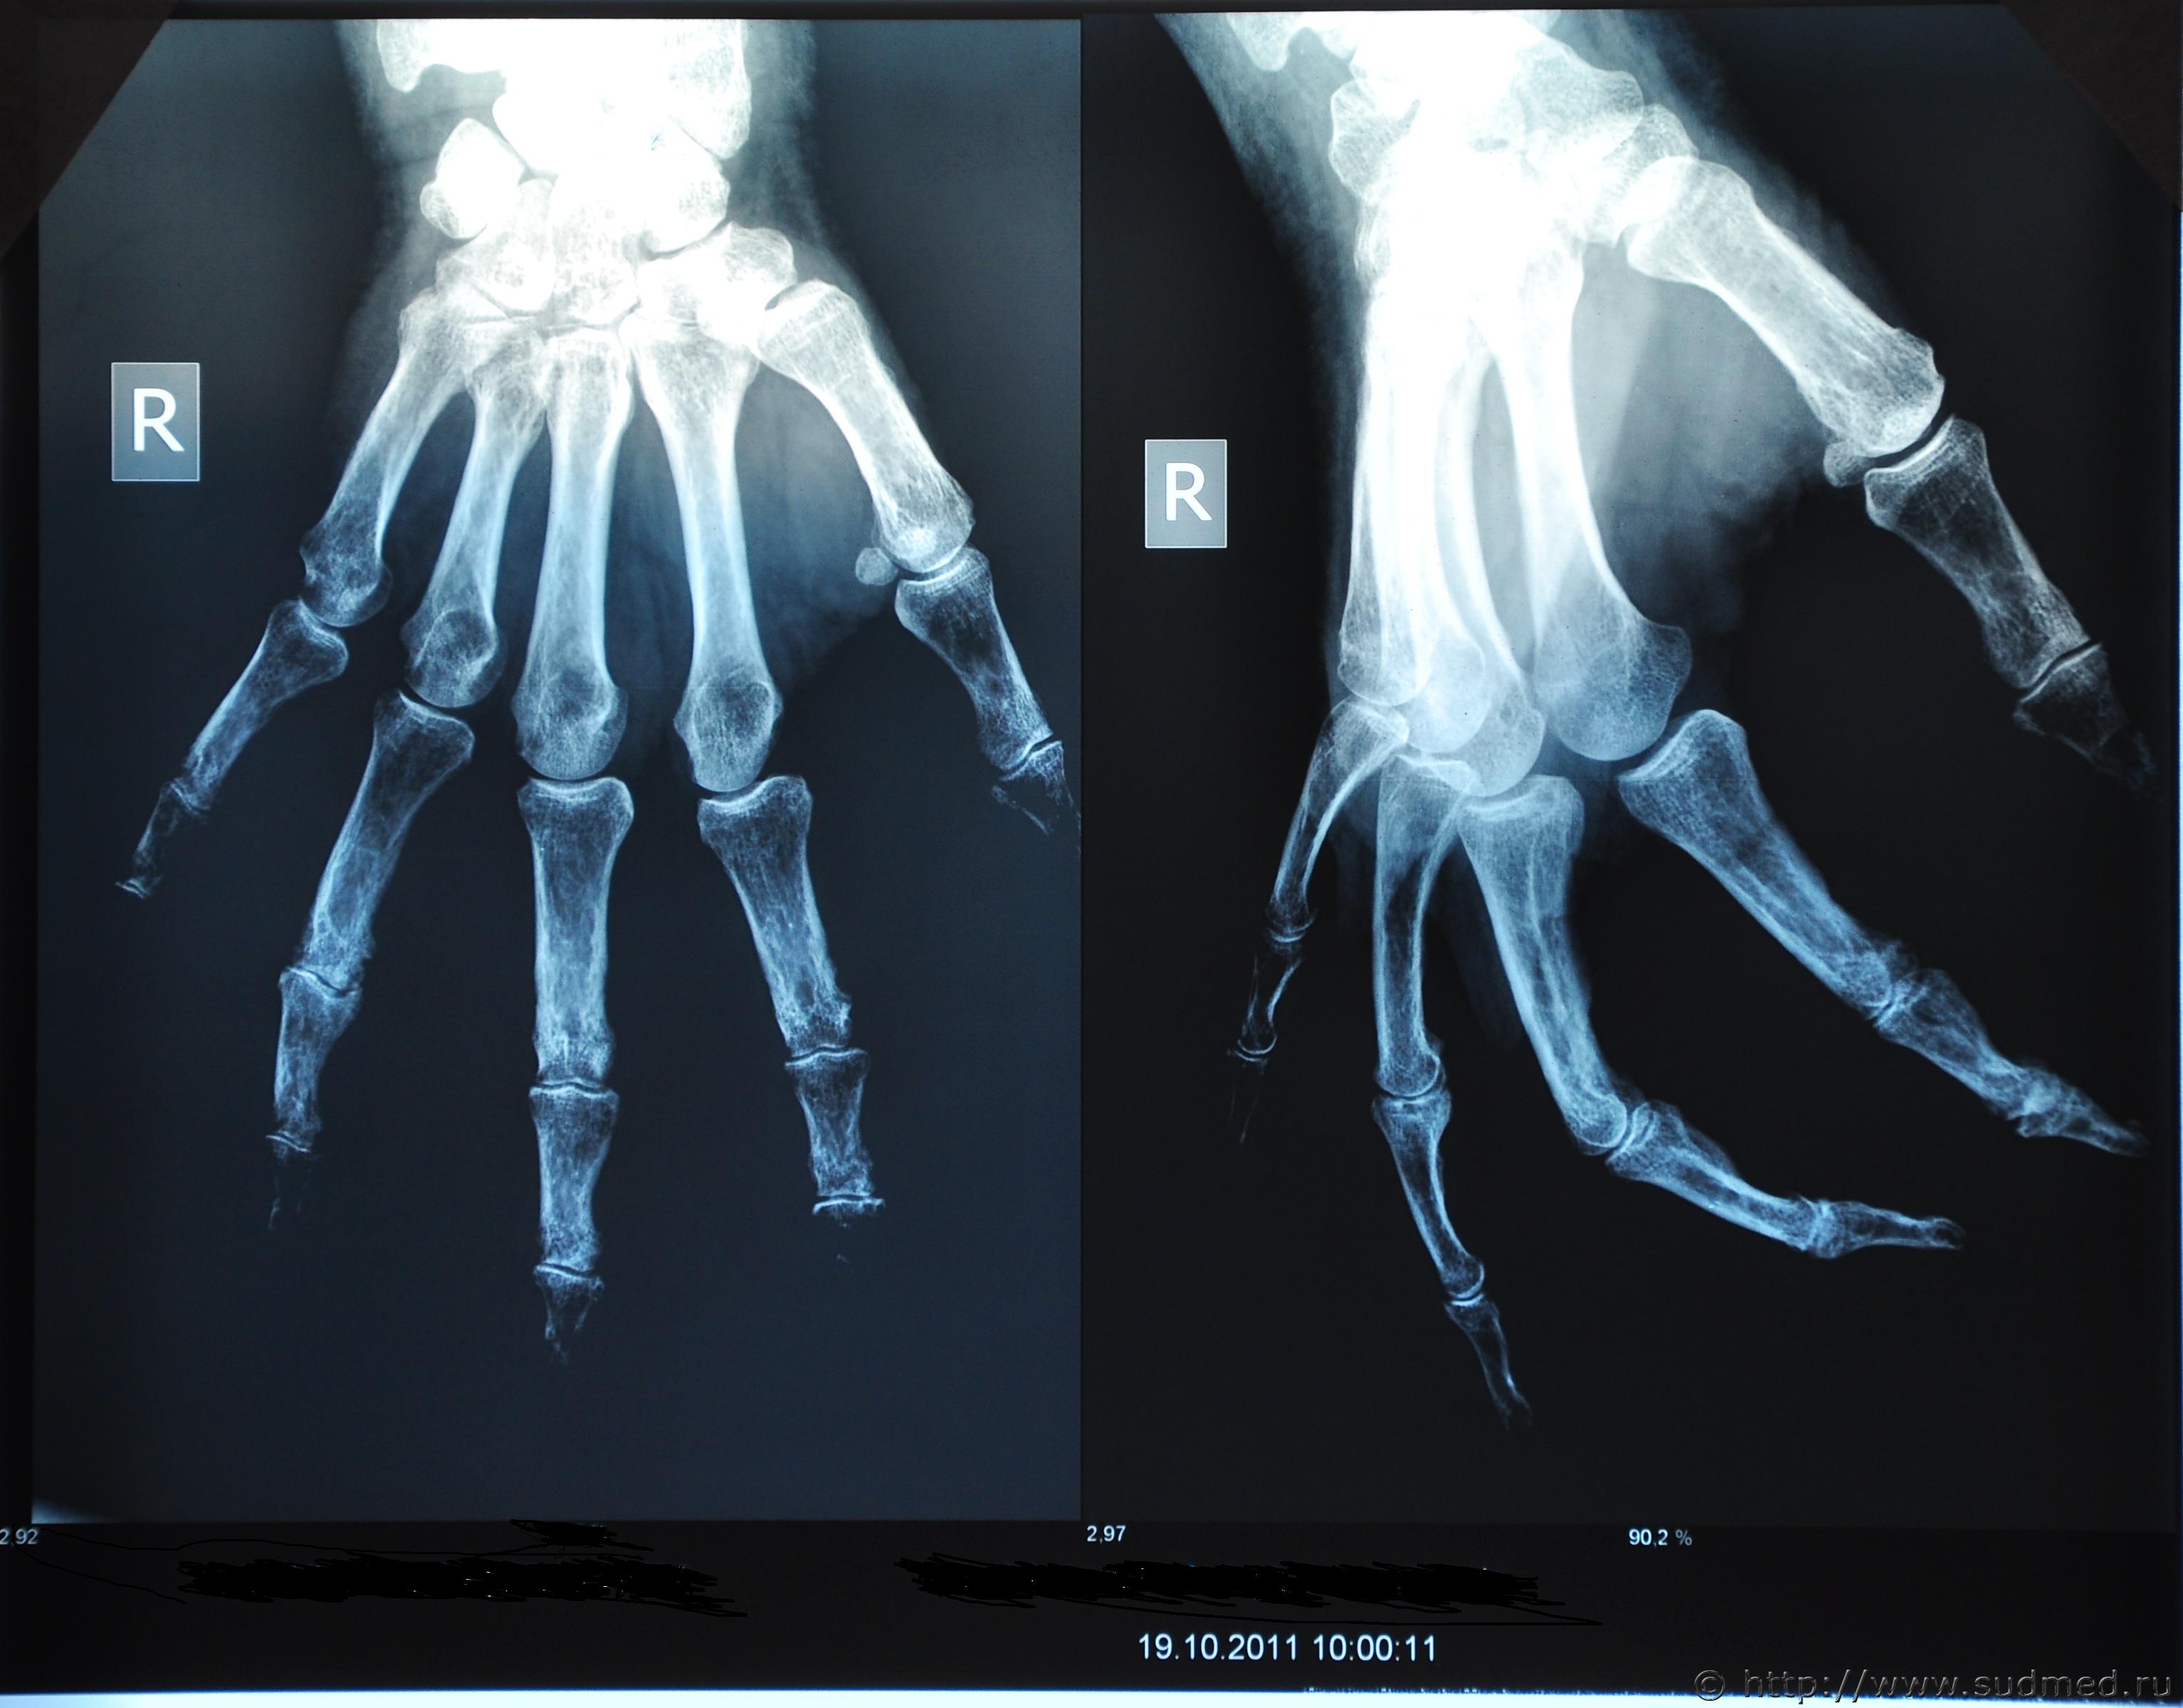

"краевой внутрисуставный перелом проксимального конца средней фаланги четвертого пальца правой руки"

Заодно выложите и рентгенограмму этого пальца в двух проекциях (лучше - все снимки), а то описание скромненькое, а для ответа на вопрос №1 подробности не помешают. По вопросу №2: травматолог обучен лечить переломы, а не разбираться в том, как они могли образоваться, а суд-мед.эксперт профессионально подготовлен, в том числе, для установления того, как могло быть причинено повреждение. Эксперт-травматолог хорош, когда в экспертизе исследуется вопрос о правильности лечения пациента травматологического профиля.

снимки выложила , они не свежие, а после консолидации перелома.